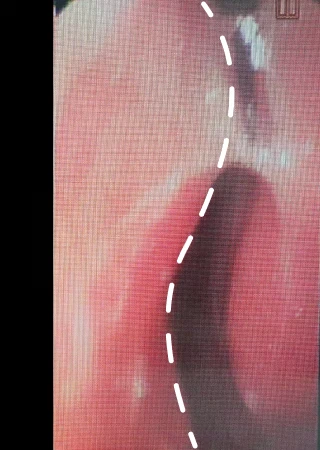

코의 중앙에는 수직으로 위치하여 콧구멍을 둘로 나누는 벽인 비중격이 있습니다. 비중격만곡증이란 비중격이 휘어져 있어 좁아진 쪽의 세포벽이 두꺼워져서 공기의 흐름이 원활하지 못한 것을 말합니다. 대부분의 비중격만곡증은 좌우가 교대로 하여 코가 자주 막히는 증상을 보이며, 잠을 자기 위해 옆으로 눕게 되면 누운 방향의 코가 막히는 증상이 나타납니다.

Natural 숨+ 비중격만곡증 수술 방법

휘어진 곳의 비중격 연골 절개 후 제거

휘어진 비중격 연골을 제거된 공간으로 펴줌

비중격이 완전히 펴진 상태 완성